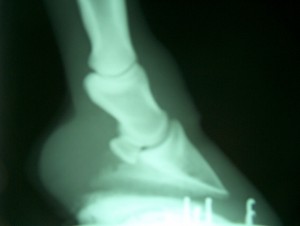

He treats a wide variety of hoof and limb problems in foals, mature active horses and older patients, as well as making recommendations for routine trimming and shoeing to allow your horse to move in the best way possible. He is experienced in treating conditions such as laminitis (founder), navicular disease, and issues with hoof growth that are best helped with both special horseshoeing techniques and sometimes medications. Dr. Dean can provide the best in horseshoeing care for horses with special hoof needs. Dr. Dean’s farrier experience has made him exceedingly proficient at “hot shoeing” and can shape your horses shoes in his mobile forge to fit exactly. An example of successful treatment of a severe hoof crack is exhibited below.